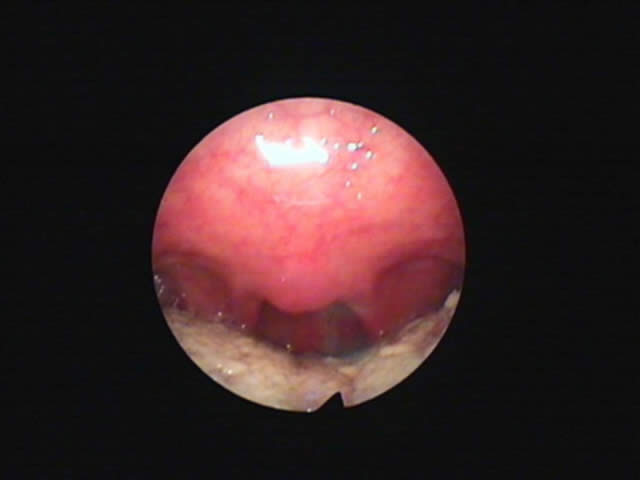

1) 手術前、口蓋垂(のどちんこ)が太く長く舌にくっついており、その横の粘膜も幅が広い。いびき改善手術をすることとなりました。 2) 外来(日帰り手術)手術後50日、70%のいびき音が改善したと本人がいっております。のどがひろくなりました。

1) 手術前 37歳男性 2) 外来(日帰り手術)手術後45日、いびきはほとんど消失